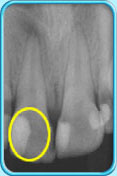

图中所见是一张X光片,显示一颗牙髓已坏死的乳臼齿。治疗前